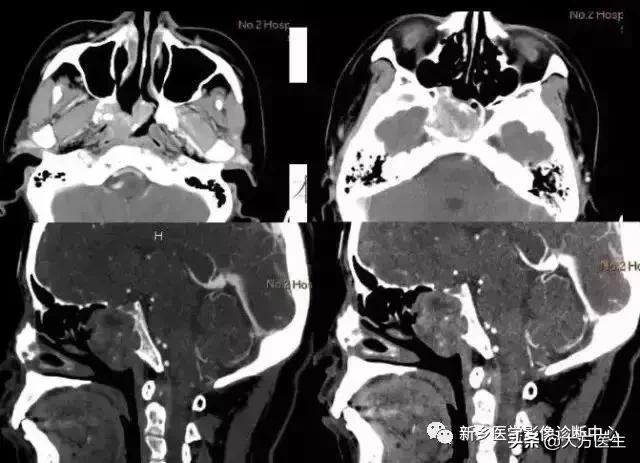

3、颅咽管瘤

多见于20岁以下,常有内分泌代谢障碍及视觉障碍,部分可有颅高压表现。

X:可见鞍区钙化,蝶鞍异常扩大及颅高压征象。CT:见囊实性肿块,囊壁斑块、蛋壳样钙化。MR:T1高等低混杂信号,T2为高信号。